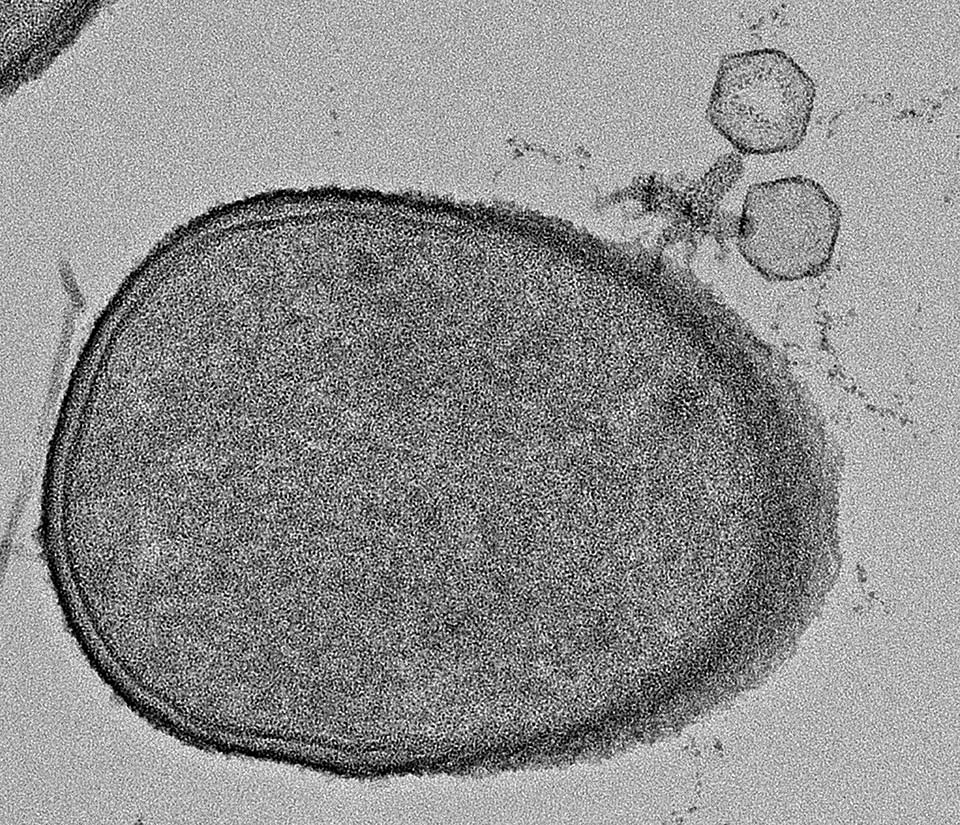

לחוש הריח שמור תפקיד מרכזי בחיזור ורבייה ביונקים. בשנת 1959, גילתה הזואולוגית הבריטית הילדה ברוס כי נקבות של מכרסמים נוטות להפיל את עובריהן בתגובה לריח גוף של זכר זר. מאז הגילוי הראשוני, התגלה "אפקט ברוס" גם במינים נוספים של יונקים ובהם מין מסוים של קופים. הסיבה לאפקט ברוס אינה ידועה במלואה, אך ההסבר האבולוציוני הנפוץ הוא שהנקבה "בוחרת" לסיים את ההריון שלה, לאחר שהבינה כי בא לשכונה זכר חדש – וכשיר יותר – מאשר הזכר שהפרה אותה. גם בבני-אדם ישנן עדויות למעורבות של חוש הריח ביחסים בין המינים. לפיכך, ביקשו במעבדתו של פרופ' סובל לבדוק אם ייתכן אפקט דומה גם בנשים הסובלות מהפלות חוזרות בלתי-מוסברות.

תנאי הכרחי לקיומו של אפקט ברוס במכרסמים, הוא כמובן היכולת של הנקבה לזכור את ריח הגוף של הזכר שהפרה אותה. כדי לבדוק זאת בבני-אדם, הציגו החוקרים לנשים שעברו הפלות חוזרות בלתי-מוסברות ריחות שחולצו מחולצות טריקו שלבשו בני הזוג שלהן לצד ריחות שחולצו מחולצות של גברים זרים. החוקרים גילו כי נשים אלה הצליחו לזהות את בן הזוג שלהן על-פי ריח הגוף, בעוד נשים בקבוצת הביקורת לא הצליחו בכך; מלבד יכולת זו, נשים אלה ניחנו בחוש ריח טוב אך במעט מהנשים בקבוצת הביקורת. "למעשה, היכולת שלהן לזהות את הריח של בן הזוג הייתה כה מדהימה, עד שכמה מהן אמרו לנו 'אוי, בעלי כאן' לאחר שנחשפו לריח שהצגנו להן – וזאת מבלי שידעו כלל מה הן מריחות", מספרת רעות וייסגרוס, שהובילה את המחקר לצד ד"ר לירון רוזנקרנץ וד"ר טלי וייס. "זה לא קרה, אף לא פעם אחת, בקבוצת הביקורת".

בדיקות נוספות העלו כי נשים אלה לא רק טובות יותר בזיהוי הריח של בן הזוג שלהן, אלא שהן תופסות ריח גוף של גברים באופן שונה מהנשים בקבוצת הביקורת. כאשר התבקשו לדרג את ריחות הגוף של גברים על-פי מדדים שונים, ממדדים סטנדרטיים של נעימות ועוצמה ועד משתנים כגון משיכה מינית או מידת הפוריות, הנשים שסבלו מהפלות חוזרות היו ייחודיות באופן שתיארו ודירגו את הריחות, ותפיסת הריח שלהן הייתה שונה באופן משמעותי מקבוצת הביקורת. יתירה מכך, בסריקות MRI שנערכו לנשים אלה התגלה כי פקעות ההרחה שלהן – התחנה הראשונה במסלול העצבי מהאף למוח קטנות יותר בממוצע. בנוסף, סריקות fMRI, הראו תגובה מוגברת לריחות גופם של גברים בהיפותלמוס שלהן, האזור המוחי האחראי על ויסות הורמונלי, ובכלל זאת גם במהלך ההריון, אשר ממלא תפקיד מפתח באפקט ברוס במכרסמים.